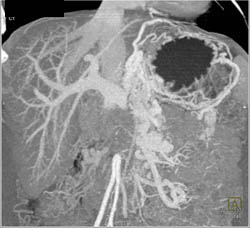

Portal Vein (PV) Thrombosis and Chronic Pancreatitis